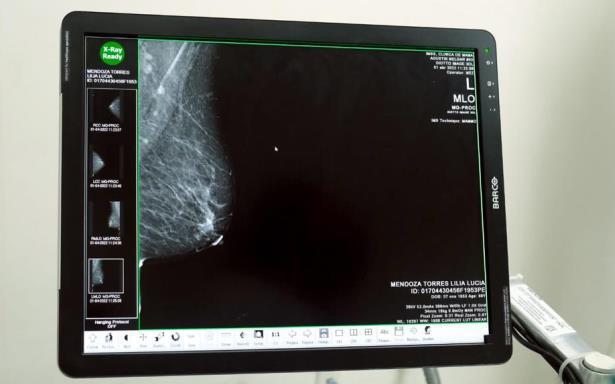

Desde la apertura de la primera Unidad en 2016 y hasta el año pasado se han realizado más de 458 mil 227 mastografías, 161 mil 375 ultrasonidos, 171 mil 815 evaluaciones diagnósticas, 17 mil 815 estudios de biopsia y citología, así como la detección de cinco mil 986 casos positivos, de los cuales 639 fueron in situ.

La especialista mencionó que a las pacientes con diagnóstico de sospecha BIRADS 4 y 5 (sistema para describir los resultados y hallazgos de las mastografías), así como aquellas a quienes se les realiza una biopsia que se envía a análisis al Servicio de Anatomía Patológica, se les gestiona una cita prioritaria en su hospital de Segundo o Tercer Nivel con el oncólogo y se inicia tratamiento en 21 días o menos, desde el momento de la detección.

• Inicio de mastografía de tamizaje de mujeres a partir de los 40 años con especial atención al grupo blanco de 50 a 69 años de edad sin síntomas de la enfermedad.

• Diagnóstico oportuno para todas las mujeres con resultados anormales ya sea por estudios de imagen como mastografía o por la exploración clínica por profesional de la salud.